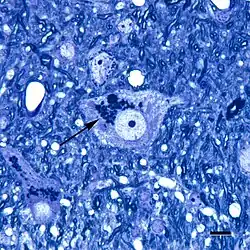

Lipofuscin is the name given to fine yellow-brown pigment granules composed of lipid-containing residues of lysosomal digestion.[1][2] It is considered to be one of the aging or "wear-and-tear" pigments, found in the liver, kidney, heart muscle, retina, adrenals, nerve cells, and ganglion cells.[3]

Lipofuscin appears to be the product of the oxidation of unsaturated fatty acids and may be symptomatic of membrane damage, or damage to mitochondria and lysosomes. Aside from a large lipid content, lipofuscin is known to contain sugars and metals, including mercury, aluminium, iron, copper and zinc.[4] Lipofuscin is also accepted as consisting of oxidized proteins (30–70%) as well as lipids (20–50%).[5] It is a type of lipochrome[6] and is specifically arranged around the nucleus.